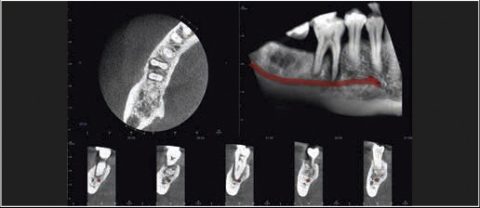

Tomografia komputerowa jest niezastąpiona w planowaniu leczenia implantologicznego i chirurgicznego. W wielu przypadkach pozwala uniknąć powikłań podczas leczenia kanałowego jeszcze przed jego rozpoczęciem. Wysokiej rozdzielczości badanie mikroCBCT (endoCBCT) precyzyjnie obrazuje architekturę systemu kanałowego zęba. Na jego podstawie lekarz może ocenić ilość kanałów, ich krzywiznę oraz ewentualne połączenia.

Cztery różne pola obrazowania zapewniają niezawodną diagnostykę 3D w całym obszarze jamy ustnej. Zapewniają one precyzyjne dopasowanie, odpowiednie do wskazań a także uniwersalne możliwości zastosowania w codziennej praktyce – od endodoncji, poprzez implantologię do chirurgii jamy ustnej.